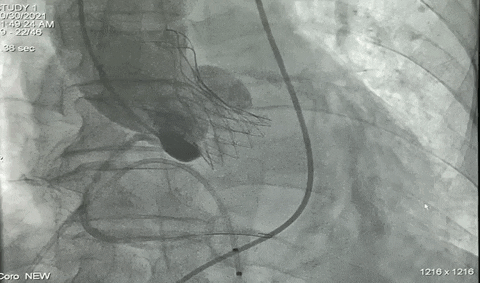

球囊预扩

瓣膜释放过程